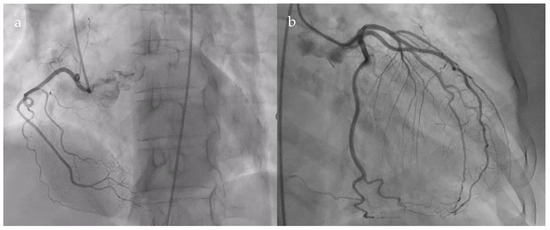

The patient underwent coronary angiography to exclude an ischemic cause of the dyspnea. Coronarography showed normal epicardial coronary arteries (Figure 2).

Figure 2.

Normal coronary angiogram. (a). Right coronary artery; (b). Left main coronary artery, anterior descending artery, circumflex artery, and collateral branches.